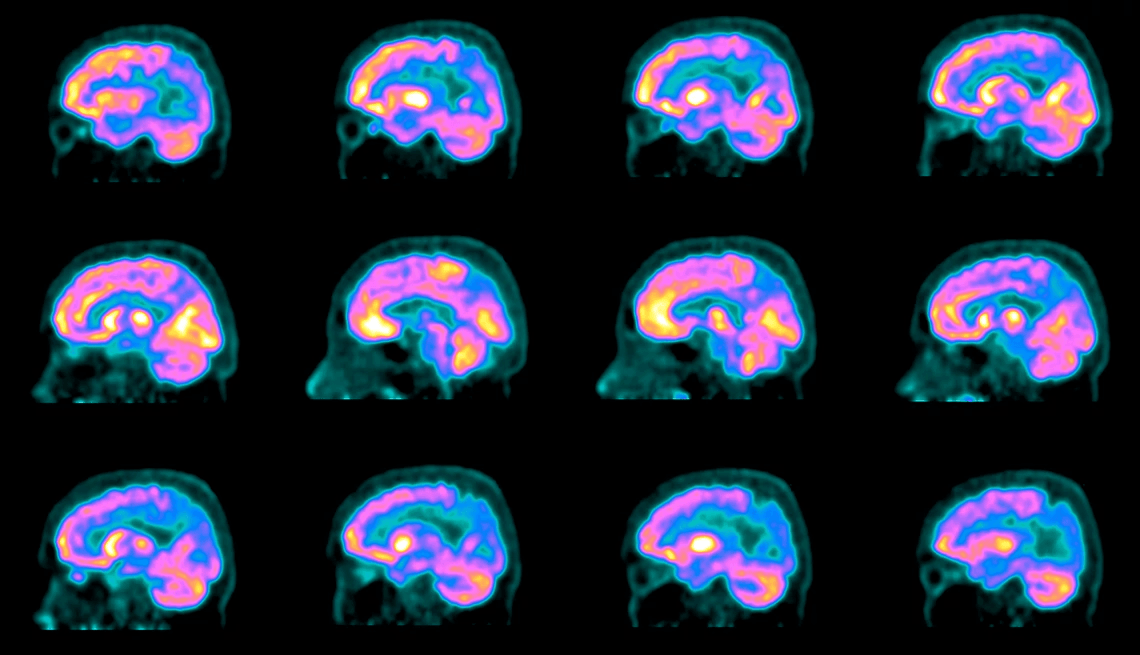

For the first time, a randomized, controlled, peer-reviewed clinical trial demonstrated that an intensive lifestyle intervention (without drugs) may significantly improve cognition and function in many patients with mild cognitive impairment or early dementia due to Alzheimer’s disease.